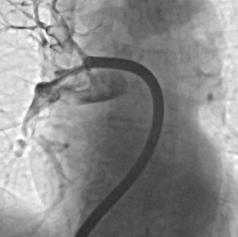

V Splošni bolnišnici Murska Sobota so naredili pomemben korak v razvoju sodobne medicine, saj so uspešno izvedli prvo mehansko odstranitev krvnega strdka iz pljučne arterije.

Poseg je opravil interventni kardiolog Danijel Crnčić ob podpori zdravnikov internistov kardiologov, Urške Bencak Ferko in Dušana Kovača ter celotne ekipe interventne kardiologije, kar predstavlja pomemben mejnik za zdravljenje ene najnevarnejših žilnih bolezni.

V zadnjih letih pa se vse bolj uveljavlja sodobnejši pristop, to je mehanska odstranitev strdka s katetrom. Gre za minimalno invaziven poseg, pri katerem zdravnik skozi veno, običajno v dimljah, uvede kateter in ga pod nadzorom vodi do mesta zapore. Nato s posebnim sistemom ustvari podtlak in strdek fizično odstrani iz žile.

Foto: Splošna bolnišnica Murska Sobota